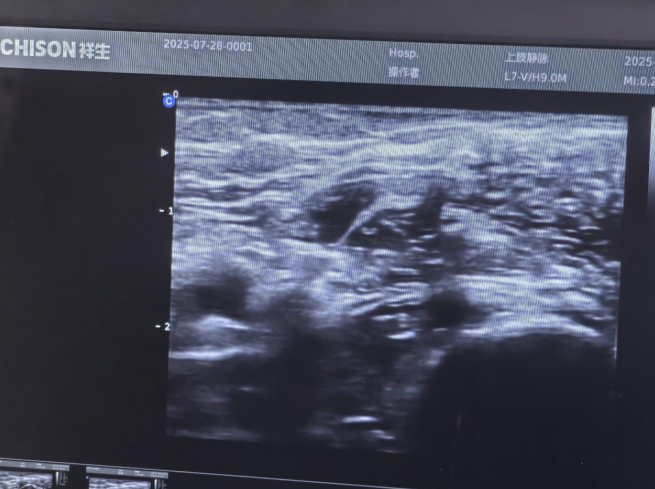

臂丛麻醉DSA下动静内瘘球囊扩张术能够清晰地显示臂丛神经的结构及其与周围组织的关系,可缩短穿刺时间,减少并发症,提高麻醉成功率,并提供良好的镇痛效果。此外,超声(DSA)引导下的臂丛神经阻滞能够降低交感神经的兴奋性,扩张血管,减少术中血管痉挛,对于内瘘介入治疗患者来说尤为适宜。

获知该技术的优势后,7月28日,汪女士接受了“无痛”的DSA下动静脉内瘘狭窄球囊扩张术。在整个手术过程中,汪女士只感受到一定的压力,但疼痛明显被有效控制。术后,汪女士表示,本次术中“无痛”体验与上次局部麻醉的感受可谓天壤之别。术后第二天,她就顺利地接受了常规血液透析。